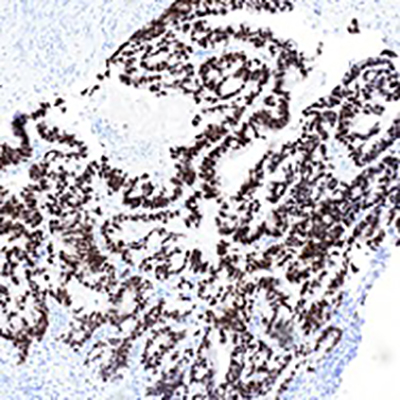

Histopathologic examination showed fragmented specimen containing adenocarcinoma, characterized by relatively well formed glands with cribriform glands in some areas. The epithelial cells were relatively uniform with basally oriented nuclei and intracytoplasmic mucin was present in a subset of cells. Some areas contained areas of necrotic cellular debris within the lumens of the neoplastic glands. No areas of non-atypical endometrial hyperplasia or endometrial intraepithelial neoplasia were identified. There were fragments of leiomyomas in the background. Immunohistochemical analysis demonstrated the adenocarcinoma cells to be positive for CK20, CDX-2, SATB-2 (patchy), MUC2 (patchy) and CEA. They were negative for CK7, PAX-8, GATA-3, ER, PR, Vimentin and hrHPV in-situ. The p16 and MUC6 showed rare positive neoplastic cells, and p53 demonstrated a wild type pattern. Mismatch repair proteins were intact. The combined morphologic and immunohistochemical features support and adenocarcinoma with an enteric/gastrointestinal phenotype. The case was finalized as moderately differentiated adenocarcinoma with intestinal/enteric phenotype. In the absence of any notable conventional endometrioid adenocarcinoma or precursor endometrial proliferation, the differential diagnosis included a metastasis (likely from colorectal origin or other sites which may acquire an intestinal phenotype, and an unusual primary endometrial carcinoma with pure intestinal metaplasia/differentiation. Additional workup to exclude extrauterine primary sites was recommended.

Fig. 1 Adenocarcinoma embedded in endometrial stroma (A and B). Adenocarcinoma with dirty necrosis (C) and intracytoplasmic mucin (D). The malignant cells are negative for CK-7 (E) and positive for CK-20 (F), CDX-2 (G), SATB-2 (H).